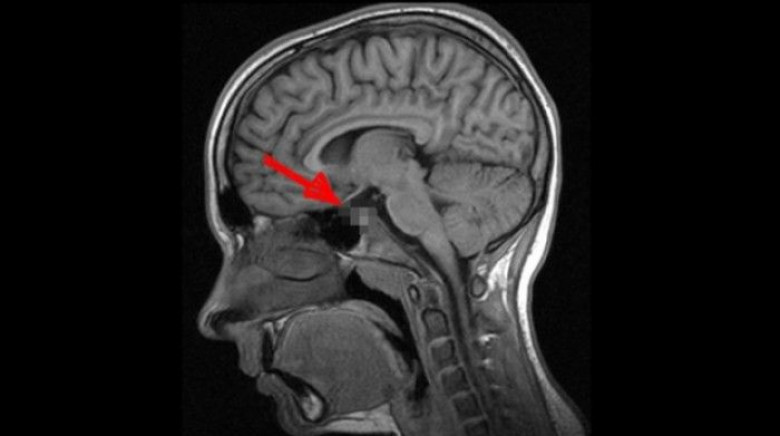

Գիտնականները հայտարարել են, որ ուղեղի այս հիվանդությամբ տառապում է մարդկանց գերակշիռ մեծամասնությունը

Դեժավյուն հոգեբանական կարգավիճակ է, որի ընթացքում մարդուն թվում է, թե նա էլի է հայտնվել նման իրավիճակում: Երևի Ձեզ հետ էլ է պատահել նման բան՝ որևէ անծանոթ տուն կամ վայր առաջին անգամ եք ոտք դրել, սակայն Ձեզ թվացել է, որ այդտեղ արդեն եղել եք:

2009 թ. գիտնականները որոշեցին լրջորեն ուսումնասիրել այս ոչ սովորական երևույթը: Որոշ ժամանակ անց Մասաչուսեթսի տեխնոլոգիական համալսարանի մասնագետները հայտարարեցին, որ ուղեղն ունի այնպսիս հատված, որը պատասխանատու է այս երևույթի համար: Դեժավյուի գլխավոր դերը այն նեյրոններինն է, որոնց շնորհիվ կարողանում ենք զգալ պատկերների ամենափոքր տարբերություններն անգամ: Սրա շնորհիվ մարդը գիտակցում է, թե ինչպիսի տպավորություններ է ինքը վաղուց արդեն ստացել, իսկ որոնք են ամբողջապես նոր նրա համար: Այսն կարծես մարդու «կյանքի փորձառությունը» բաժանում է անցյալի և ներկայի: Սակայն երբ երկու տպավորություններ իրար շատ նման են լինում, ուղեղի այդ հատվածի աշխատանքը «կախում է», ինչն էլ բերում է տարօրինակ այս զագցմանը:

2009թ. բացահայտումից հետո միայն մեկ անպատասխան հարց է մնացել՝ այս երևույթը բնորոշ է առողջ մարդկա՞նց, թե՞ ոչ այնքան: Պատասխանը գտնելու պատասխանատվությունն իրենց վրա վերցրին Չեխիայի Մասարիկա և Մեծ Բրիտանիայի Էկսետերի համալսարանների մասնագետները: Նրանք պարզեցին, որ դեժավյու կարող է լինել անգամ փոքր տարիքում, երբ նոր կազմավորվում է ուղեղը: Հոգնախության և սթրեսի ժամանակ ուղեղի տվյալ հատվածի աշխատանքը խաթարվում է և արդյունքում առաջանում են հիշողություններ այնպիսի բաների մասին, որոնք երբեք չեն էլ եղել: Գիտնականների վերջնական դիագնոզը ցավալի է՝ դեժավյուն համարվում է նյարդաբանական խանգարում: